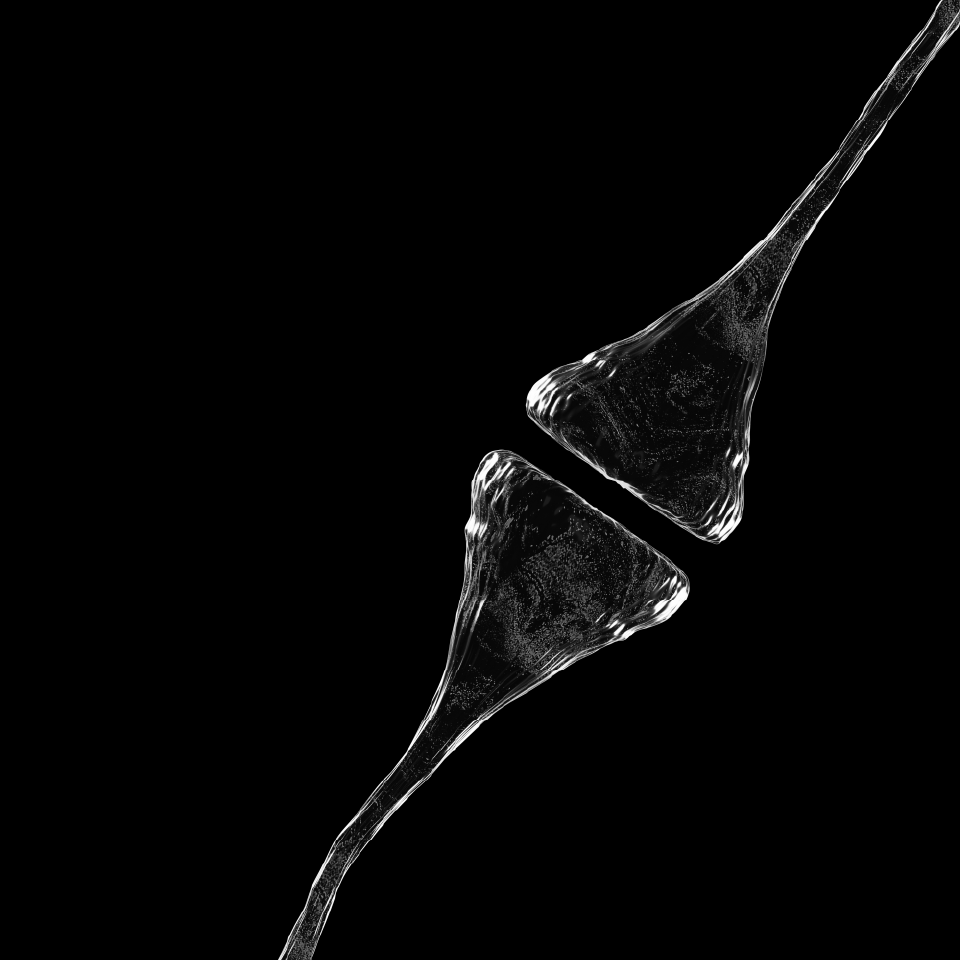

We are all quantum

Algorithmic Architecture: Strategic optimization of circuit depth and width, utilizing rigorous error-budgeting to maximize computational fidelity.

Hardware Symbiosis: Integration of direct control-layer expertise to maximize coherence intervals and optimize qubit performance.

Stochastic by nature: Advanced utilization of environmental noise as a computational asset, refining the trajectory toward optimal solutions.